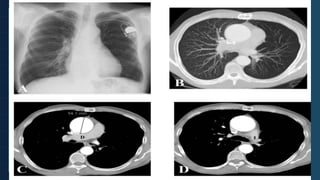

Patrón vicariante. Paciente con agenesia de la

arteria y venas pulmonares derechas y secuestro

pulmonar en lóbulo inferior derecho. A. Radiografía

simple de tórax PA. El pulmón derecho está

disminuido de volumen y en él se aprecia que su

vasculatura no sigue una distribución centrífuga y

arboriforme como en el pulmón contralateral. B.

Detalle de la radiografía anterior. La vascularización

pulmonar izquierda conforma una red

desorganizada, correspondiente a circulación

bronquial. C. Reconstrucción coronal en modo MIP

con ventana de pulmón de TC con contraste iv. Se

aprecia que la distribución de la vasculatura

pulmonar izquierda no sigue UN patrón arboriforme

como en el pulmón contralateral. D. Reconstrucción

coronal en modo MIP con ventana de mediastino de

TC con contraste iv. Se visualiza la arteria bronquial

derecha y una rama de la aorta toraco-abdominal

(puntas de flecha), la última responsable de la

irrigación del secuestro pulmonar.